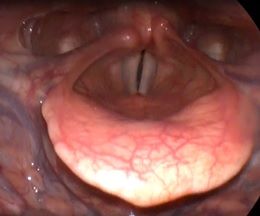

Клинический пример №2. Хирургическое лечение двустороннего паралича гортани с использованием лазера 445 нм.

Лечение данных пациентов в нашей клинике проводится по разработанному методу Кривопаловым А.А., д.м.н. зав. НИО патологии верхних дыхательных путей. Данная методика себя очень хорошо зарекомендовала.

После операции воспалительные проявления со стороны голосовой складки слабо выражены. Через месяц после операции пациенты готовы к следующему этапы реабилитации – занятие с фонопедом.

Рис 2А. Двусторонний паралич гортани. До операции.

Рис 2Б Двусторонний паралич гортани. 7 сутки после операции

Рис 2В Двусторонний паралич гортани. 1 месяц после операции